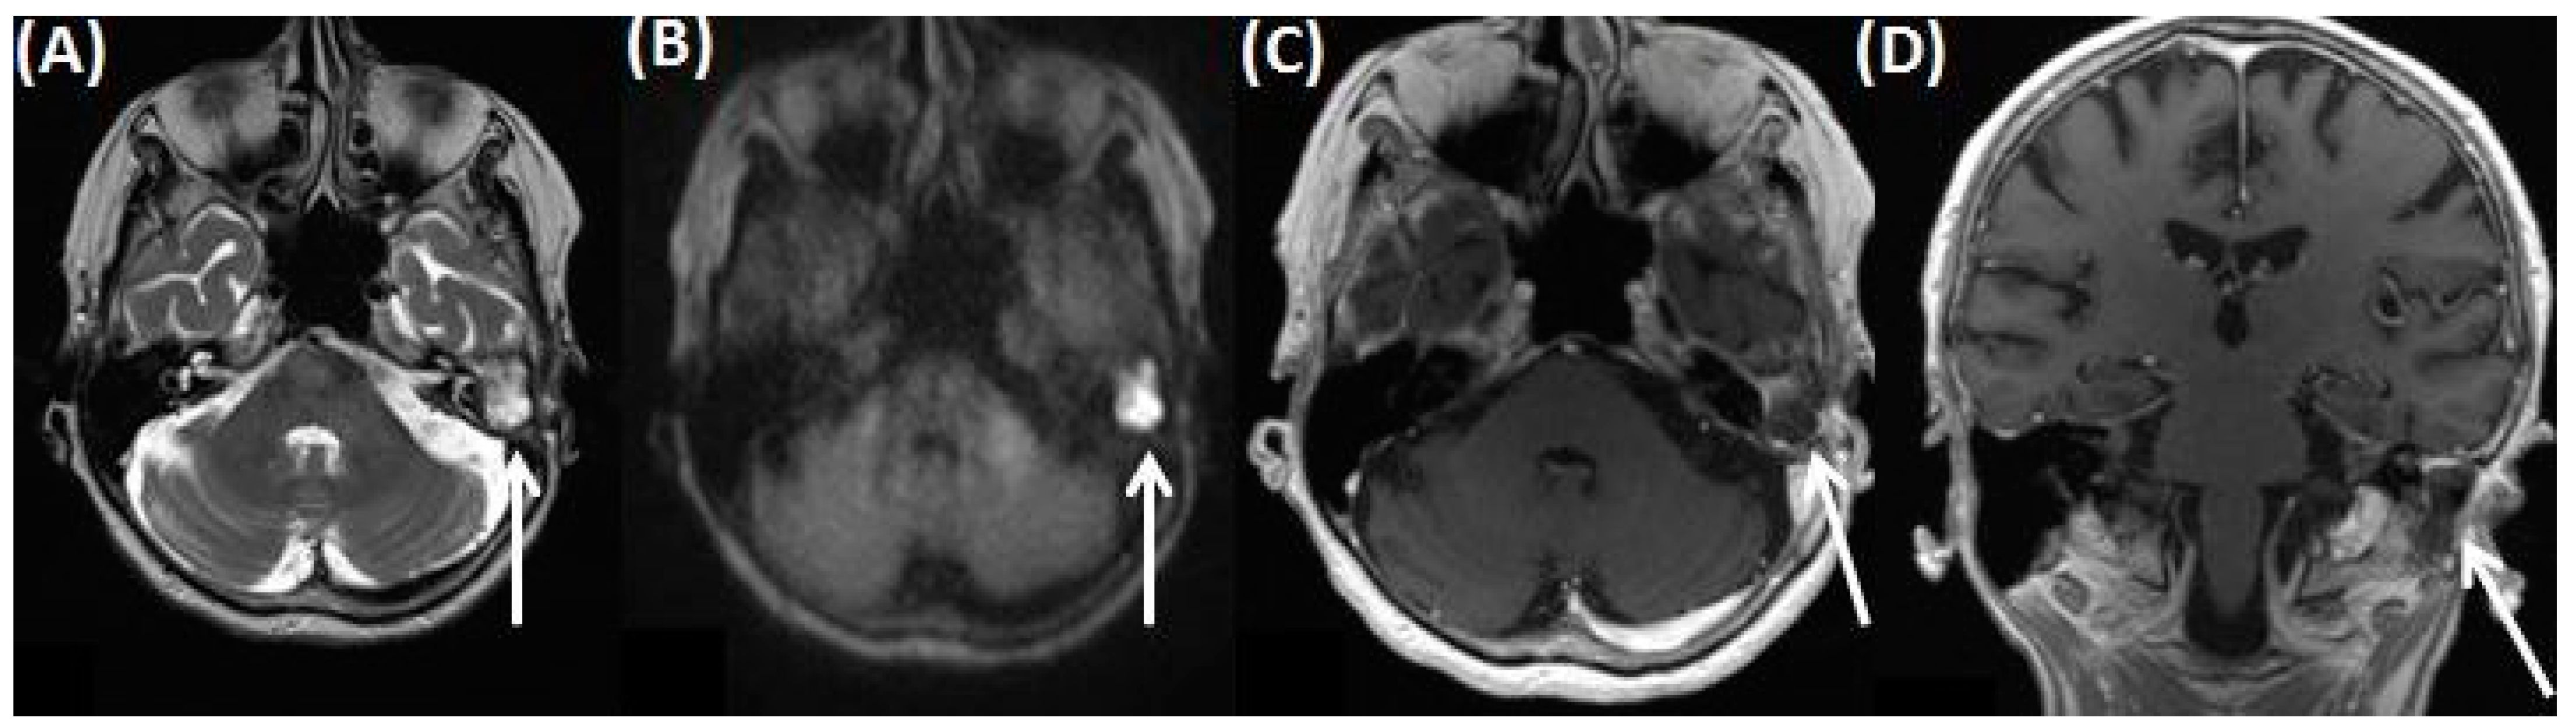

4.5. Ramsay Hunt Syndrome